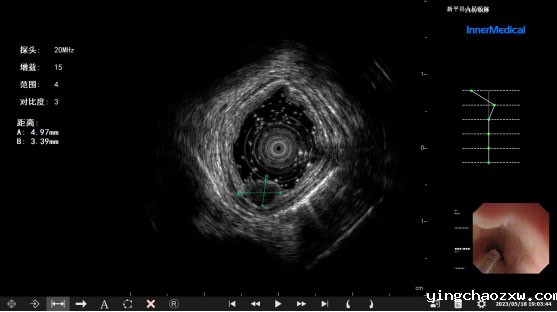

超声内镜检查